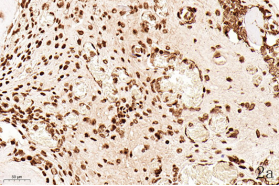

NDN(Necdin)属于黑色素瘤抗原(MAGE)家族,由60多个基因构成共享高度保守的MAGE同源结构域(MHD)[6,7]。最近几年的研究提出NDN是一种新的抑癌基因,其在卵巢癌[8]、乳腺癌[9]和黑色素瘤[10]等的组织和细胞系中低表达,过表达NDN可以抑制其生长,但NDN在骨肉瘤中的作用及机制尚不清楚。为探讨NDN在骨肉瘤中的作用及途径,我们收集了骨肉瘤患者的石蜡标本以及临床信息,对其进行了免疫组化检测及生存分析。通过对骨组织和骨肉瘤HE染色发现,骨组织组,骨密质呈板层状,陷窝中可见骨细胞呈梭形排列( 图1 a 1b) ;骨肉瘤组,瘤细胞呈多角形,核大深染,核分裂多见,瘤细胞呈车辐状排列,瘤细胞间可见少量肿瘤性骨质形成(图1c1d)。同时通过免疫组化发现,NDN表达主要位于细胞的胞核中。NDN在骨肉瘤组织中的表达率为29.4%(15/51)(图1c1d),明显低于瘤旁骨组织阳性表达率80%(8/10)(图1a1b)。